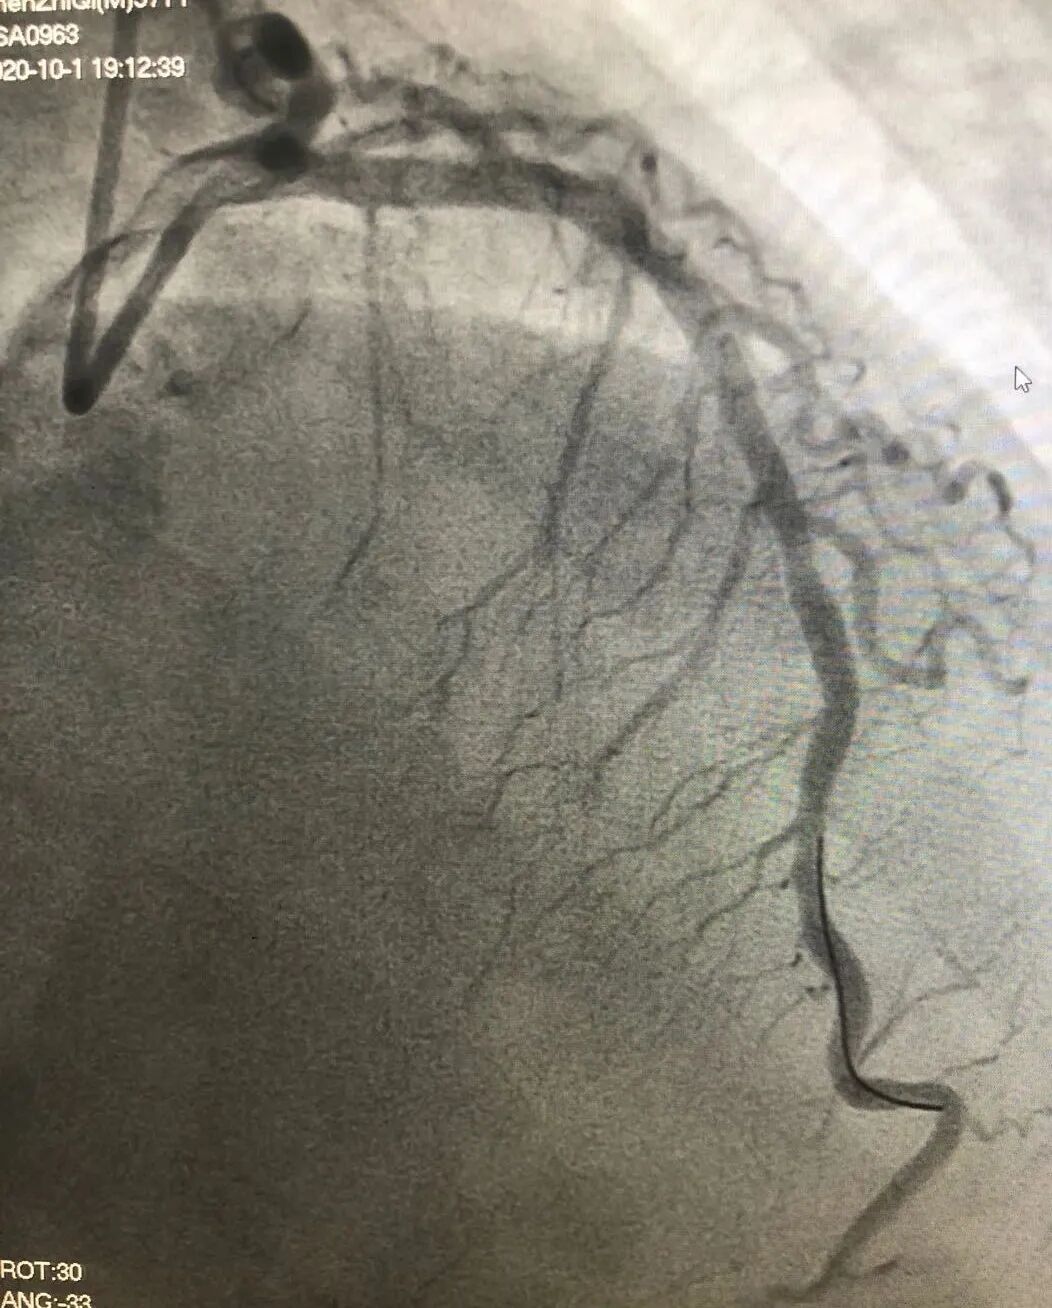

▲开通血管后血流恢复 经过一小时的惊险争战,陈先生脸色好转,胸痛消失,血压和血氧饱和度稳定,手术取得了圆满成功,一条鲜活的生命挽救回来了!死里逃生,顺利康复出院 术后,陈先生被送往心内科重症监护室进一步治疗,上呼吸机仅45小时即拔除气管导管、脱离呼吸机。